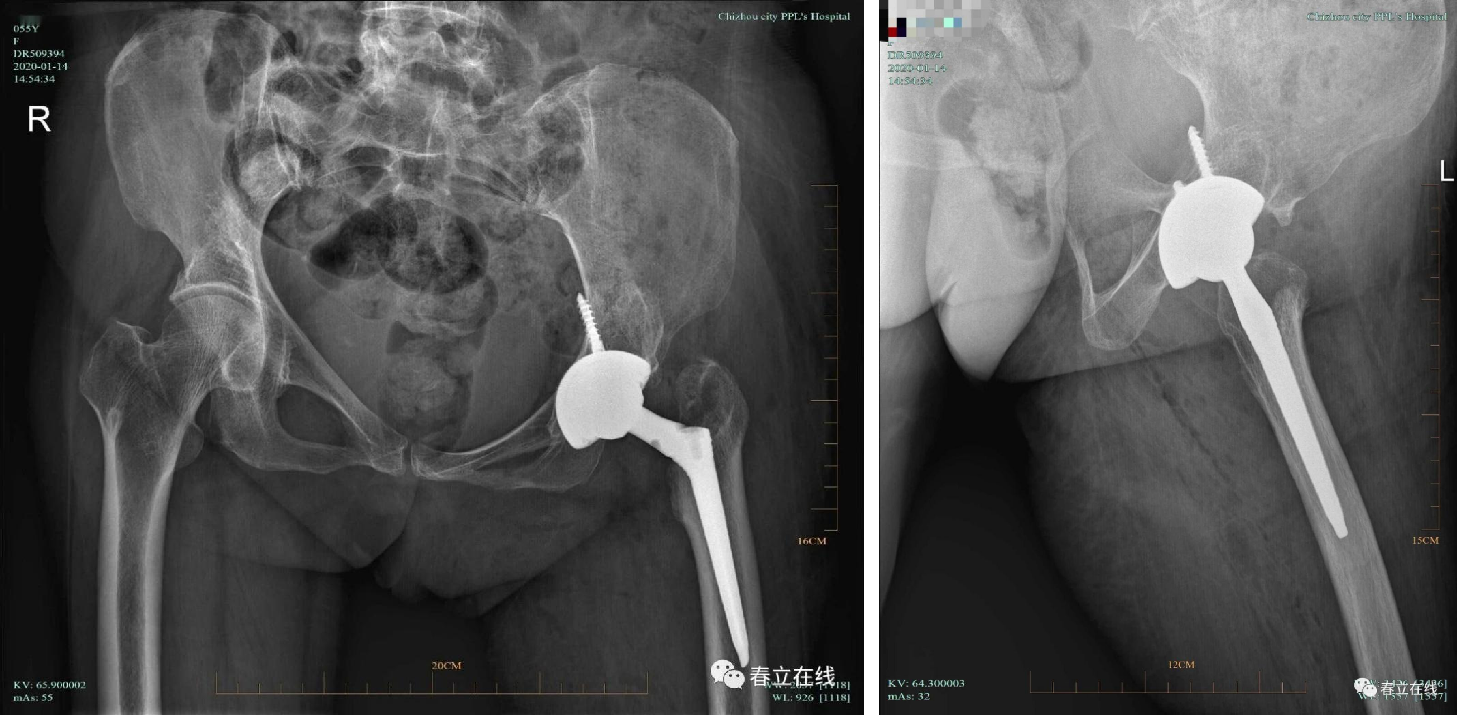

The patient is diagnosed with developmental dysplasia of the left hip (DDH), presenting with hip claudication for 50 years, left hip pain for 20 years, and symptom exacerbation over the past year. The condition has impaired her walking ability and affected daily life and physical labor, and she is scheduled to undergo left total hip arthroplasty.

Postoperative X-ray